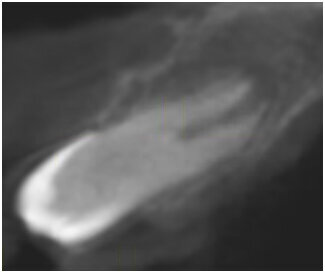

W dniu wizyty w poradni brak było oznak ostrego stanu zapalnego w okolicy 12-11. Widoczne były recesje dziąsła o wysokości 2 mm po stronie wargowej na zębach siecznych górnych przyśrodkowych, zmniejszona wysokość dziąsła zrogowaciałego do wartości 2 mm, spłycony przedsionek (Ryc. 1). Zęby były tkliwe na opukiwanie pionowe i poziome oraz wykazywały I stopień rozchwiania wg Entina. W przekrojach TK widoczny był rozległy przewlekły stan zapalny wokół wierzchołków korzeni zębów 11 i 21 (Ryc. 2), brak blaszki przedsionkowej wyrostka zębodołowego szczęki oraz resorpcja korzeni. Po wnikliwej analizie stanu miejscowego i rozmowie z rodzicami zadecydowano o ekstrakcji zębów 11 i 21 oraz w drugim etapie, ze względu na rozległy i zaawansowany proces zapalny, o autotransplantacji zawiązków 35 i 45.

Ryc. 2_TK przedzabiegowe.